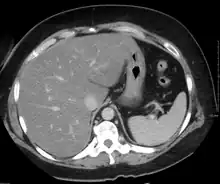

Medical imaging

On X-ray computed tomography (CT), the increased fat component will decrease the density of the liver tissue, making the image less bright. Typically the density of the spleen and liver are roughly equivalent. In steatosis, there is a difference between the density and brightness of the two organs, with the liver appearing darker.[12] On ultrasound, fat is more echogenic (capable of reflecting sound waves). The combination of liver steatosis being dark on CT and bright on ultrasound is sometimes known as the flip flop sign.

On abdominal ultrasonography, steatosis is seen as a hyperechoic liver as compared to the normal kidney.